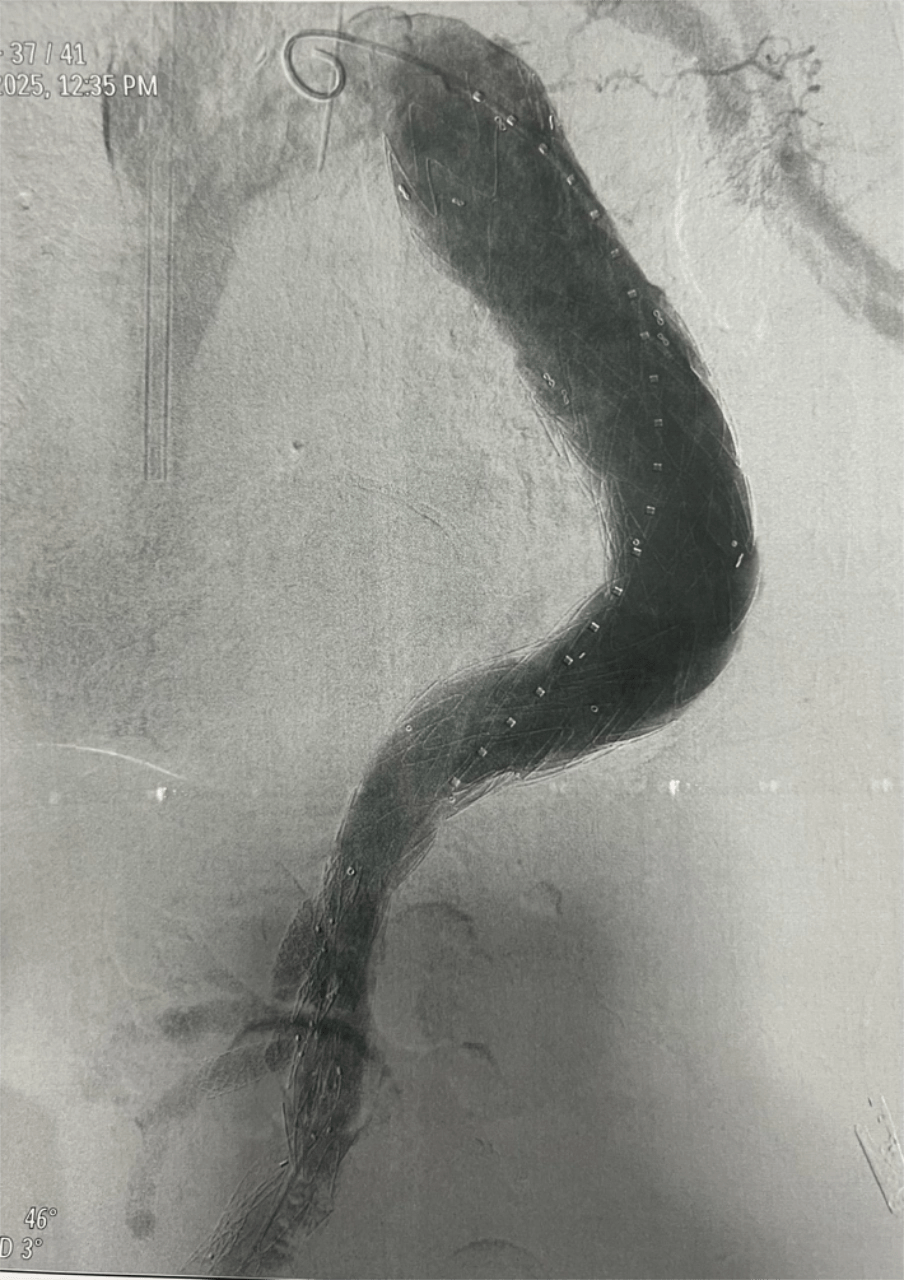

In a landmark procedure, the team successfully performed the country’s first Inner-Branch Endovascular Aneurysm Repair (iBEVAR) for the treatment of a complex thoracoabdominal aortic aneurysm on June 13, 2025, placing CGHMC among advanced vascular centers worldwide capable of performing this highly specialized technology.

The procedure involved deployment of a custom-made E-xtra Design Multi-branch (EDM) stent graft, with meticulous cannulation and sequential stenting of the visceral arteries via the left brachial approach, including the right renal, left renal, superior mesenteric, and celiac arteries. The iliac limbs were subsequently deployed and optimized with post-dilation.

This complex intervention was performed as part of a staged repair strategy, with the second stage — Thoracic Endovascular Aortic Repair (TEVAR) completed on September 18, 2025 using the Medtronic Valiant system. The staged approach was carefully planned to reduce the risk of spinal cord ischemia during treatment of the extensive thoracoabdominal aneurysm.